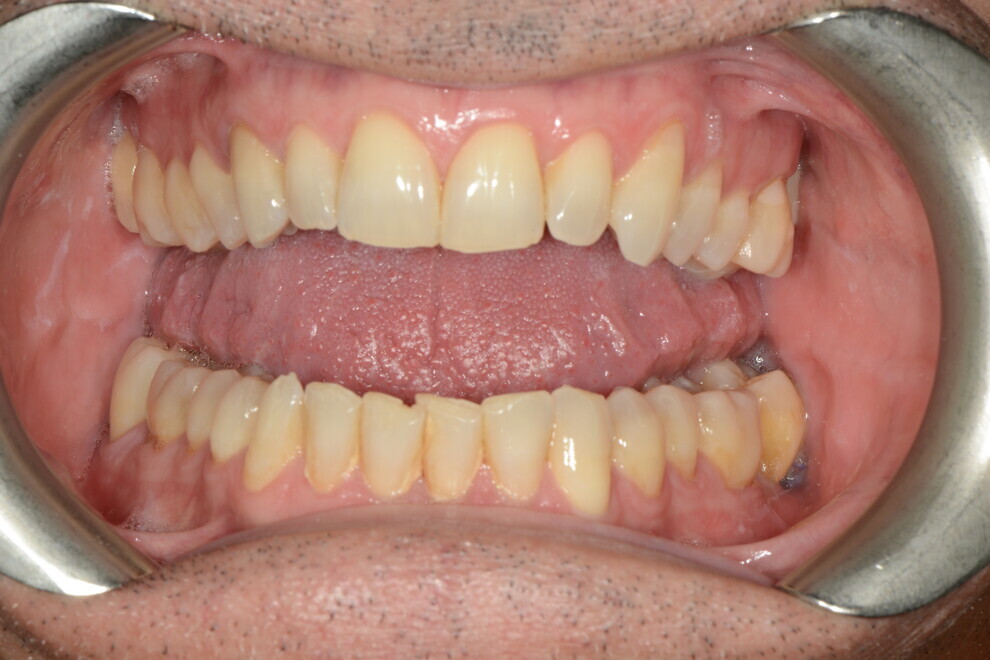

After the first phase of aligner treatment, we had achieved better inter-arch coherence, better maxillary arch expansion, and some space for improving the anterior tooth proportions restoratively (Fig. 19). We then temporarily restored the anterior teeth directly with composite, closing the spaces, improving the tooth proportions and further increasing the maxillary arch expansion (Fig. 20). We used restorative arch expansion to reduce the orthodontic destabilisation of the teeth to achieve the correct inter-arch coherence and retain the teeth in the cortical bone.38 A refinement aligner phase was undertaken to improve the final alignment of the gingival zenith and to improve the inter-arch coherence (Fig. 21). The periods of the first orthodontic phase and of the refinement were used to augment the mandibular and maxillary bone and to place the implants (Fig. 22). At the end of the orthodontic treatment, the case was finalised with ceramic veneers in the anterior area and temporary restorations on the implants in the posterior area (Figs. 23–26).

The provisional phase of about four months was important to allow the peri-implant tissue to mature and to teach the patient to chew correctly with chewing gum, cotton rolls and silicone masticatory sticks. This is fundamental training for the patient to achieve the correct alternating unilateral masticatory cycle needed to obtain the ideal rehabilitation of the masticatory system. We wanted the patient to achieve ideal masticatory and swallowing function. After sufficient rehabilitation time, we finalised the case with posterior zirconia crowns screwed on to the implants (Fig. 27).26

Our ideal final rehabilitation goals were:

• posterior stability;

• inter-arch coherence and U-shaped arches;

• anterior freedom during mastication;

• minimum disclusion vertical dimension;

• alternating unilateral masticatory cycle;

• physiological swallowing and high tongue posture against the palate; and

• mandibular disclusion advancing the mandible freely.

For maintenance purposes, after prosthetic finalisation, the patient was to carry on with the Froggymouth therapy and to use the Ri.P.A.Ra. for physiotherapeutic exercises and mastication training (Fig. 28). It was strongly recommended that the patient wear a mandibular occlusal splint during sleep. This occlusal splint was designed with disclusion guides to advance the mandible and ensure balanced contralateral support (Fig. 29).11, 39 We achieved an aesthetic appearance with adequate inter-arch coherence and a better cephalometric result (Figs. 30 & 31).